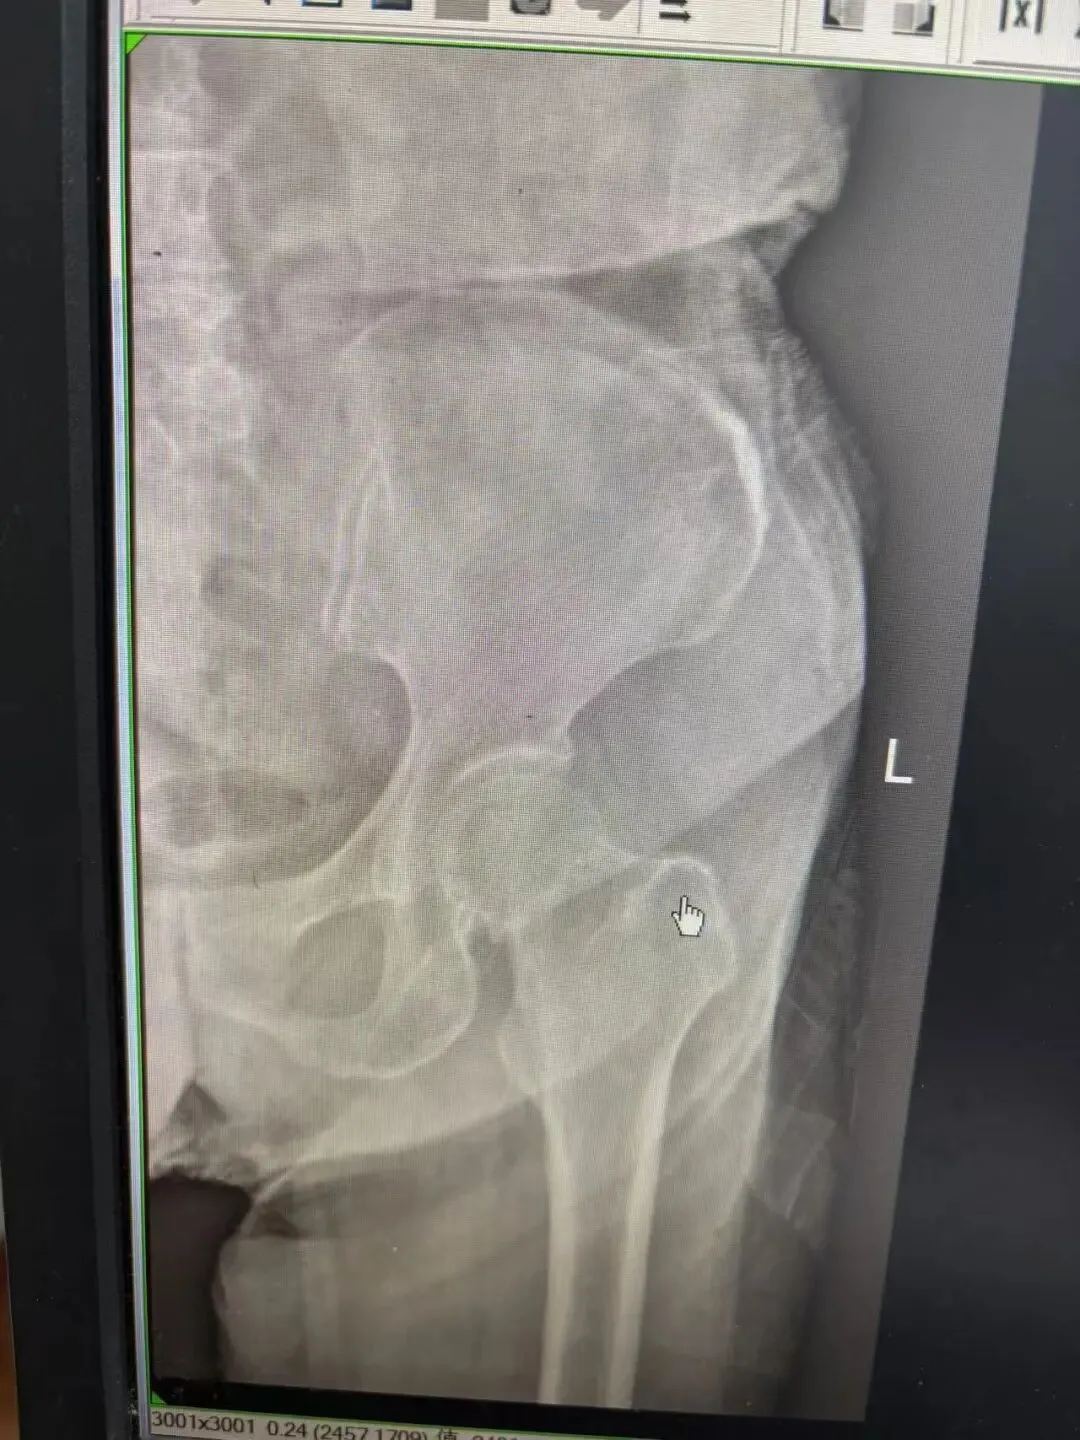

案例三:患者,女,84岁,因“摔伤致左髋部疼痛伴活动受限7小时”入院,入院后完善相关检查,诊断:左股骨颈骨折。在腰硬联合麻醉下行左人工股骨头置换术,术后恢复良好。

术前DR

术后DR